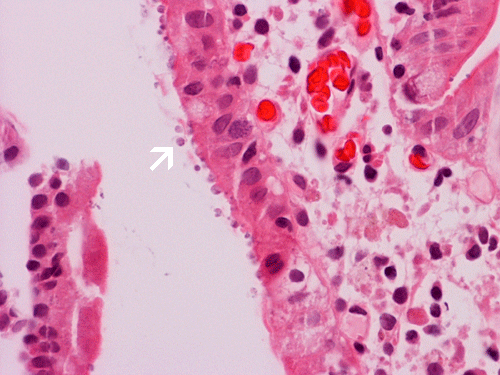

The mucosa is essentially quite normal other than some mild villus blunting in this case. There is no  abnormal inflammatory cell infiltration. However, small bead-like organisms are lining the epithelial surface (arrows in Panel A and B). With Giemsa stain, these microorganisms are positive (arrow in Panel C) and mucin droplets are negative (arrow head in Panel C).These organisms are positive for Giemsa stain. In reality, these small organisms can be identified using medium (10X) magnification if you have a high index of suspicion.

Histologically, two salient features for diagnosis of Cryptosporidium parvum are the characteristic 2 to 5 μm, mostly extracellular, basophilic bead-like spherical bodies that typically line the surface of the intestinal epithelial cells. Cryptosporidium can be found on the surface or the crypts of the small intestine. Giemsa stain is helpful in highlighting these organisms. The mucosa may have other changes including mixed acute and chronic inflammatory cell infiltration, crypt abscess formation,  villous atrophy and crypt hyperplasia. With a high index of suspicion and knowing the clinical history, Cryptosporidium can be picked up easily on medium (10X) magnification and confirmed on higher magnification. Confirmation by immunohistochemistry is helpful.